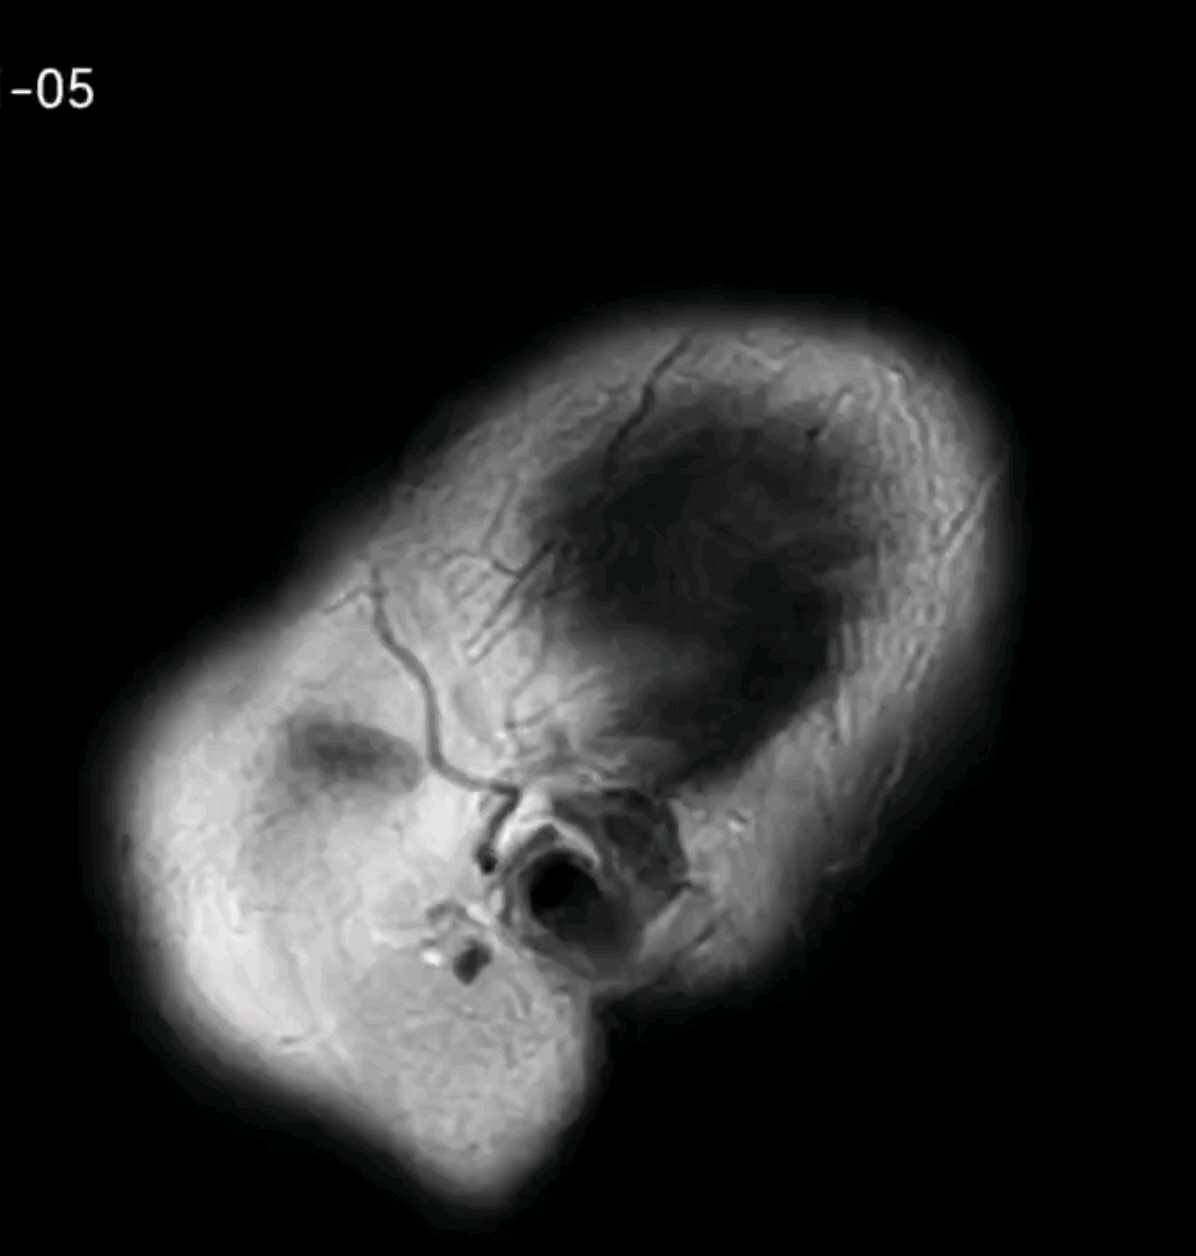

老年男性,急性起病,头痛,双耳听力下降伴胡言乱语10天余。